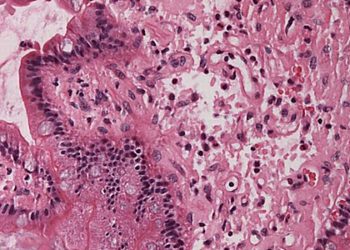

Study Rundown: Amyloidosis is a systemic disease caused by deposition of abnormal proteins in tissues leading to end organ dysfunction and significant morbidity and mortality. Involvement of cardiac muscle leads to restrictive cardiomyopathy and life-threatening arrhythmias. Hereditary transthyretin-mediated amyloidosis is an autosomal dominant cause of amyloid cardiomyopathy and polyneuropathy. Patisiran is a small interfering RNA designed to reduce hepatic production of mutant and wild-type transthyretin in patients with hATTR. The APOLLO study previously demonstrated improved quality of life and neuropathy in amyloidosis patients given patisiran. The current study is a post-hoc subgroup analysis of the APOLLO study that evaluated the change in regional myocardial strain in patients treated with patisiran versus placebo. The analysis demonstrated that treatment with patisiran was associated with decrease in LVGLS, with the greatest reduction of myocardial strain observed in the basal region.

Image: PD